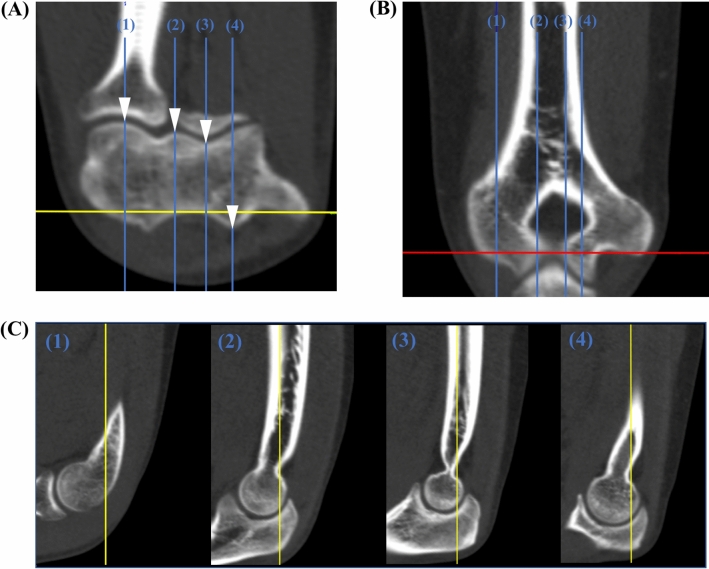

Fig. 2.

Angle measurement locations. Anatomical landmarks for definition of measurement locations are marked by white arrows in the axial view (A). Sagittal plane positioning (blue line) as applied for the angle measurement is shown for each measurement location (1–4) in the axial view with the corresponding location in the coronal view (B). Angle measurements are conducted in the sagittal view (C) in relation to the longitudinal humerus shaft axis (coronal plane: yellow line) which is depicted for each measurement location (1–4). Red line: axial plane (color figure online)

Sagittal measurement slices for angle determination were selected by positioning the sagittal plane in the axial view on defined bone landmarks at the distal humerus. The landmarks serving as measurement locations (Fig. 2), were 1) the center of the capitulum humeri, 2) the volar edge of the lateral trochlea lip, 3) the volar part of the trochlea groove and 4) the dorsal edge of the medial trochlea lip.